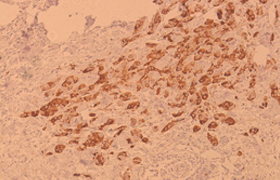

Histology (Tissue) Stem Cell Profiling

Jeevan Biosciences,Inc (JBI) has developed and characterized a novel biomarker that is specific to tumor CSCs. Using this biomarker, we are able to identify CSCs using fixed, paraffin imbedded, frozen, or fresh tumor tissue. Importantly, using our CSC specific biomarker, JBI can use nanoparticles to deliver drugs directly to CSCs, offering a targeted therapeutic option.